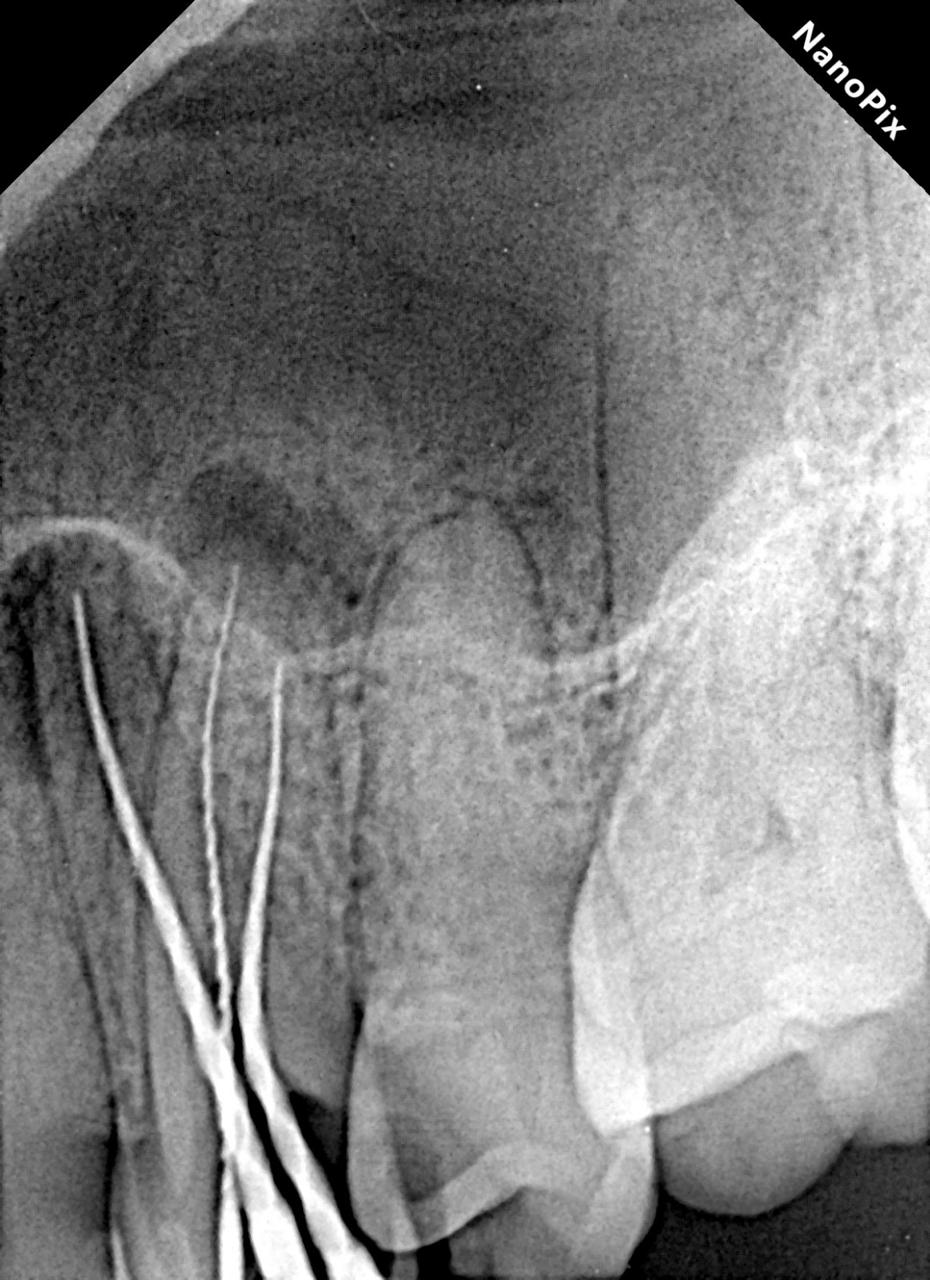

There are 2 types of x rays, intraoral and extra oral. Intraoral X rays are taken inside the mouth and an extra oral x-ray is taken outside the mouth. Intraoral X rays are more common and help your dentist in:

- Looking at the roots of teeth for root canal

- Checking bone and jaw health